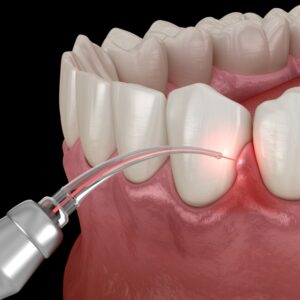

신경치료는 세균이 신경까지

침투했을 때 시행하며,

감염된 치수를 제거하고

내부를 소독해 보존합니다.